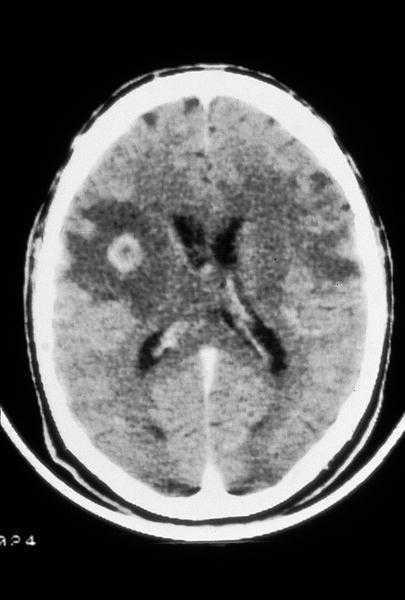

Se recomienda el inicio de profilaxis primaria en todo paciente con una cifra de linfocitos CD4 menor de 100/µl y serología positiva para T. gondii, siendo el TMP-SMX el tratamiento de elección al ofrecer también protección frente a PCP7-9. En aquellos pacientes que han tenido una toxoplasmosis encefálica (fig. 3) o de otra localización deberán mantener profilaxis secundaria siendo de elección la combinación pirimetamina-sulfadiacina junto con ácido folínico al dar protección añadida frente a la PCP7-9. En las tablas 1 y 2 se consideran otras opciones terapéuticas.

Fig. 3. TC craneal carácterística de un paciente con sida y una toxoplasmosis encefálica que presenta numerosas lesiones hipodensas; algunas de ellas captan contraste de forma anular.